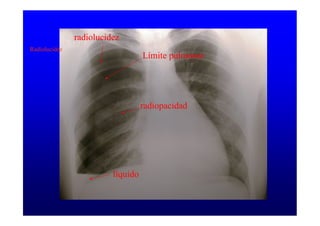

Radiolucidez

Límite pulmonar

radiopacidad

líquido